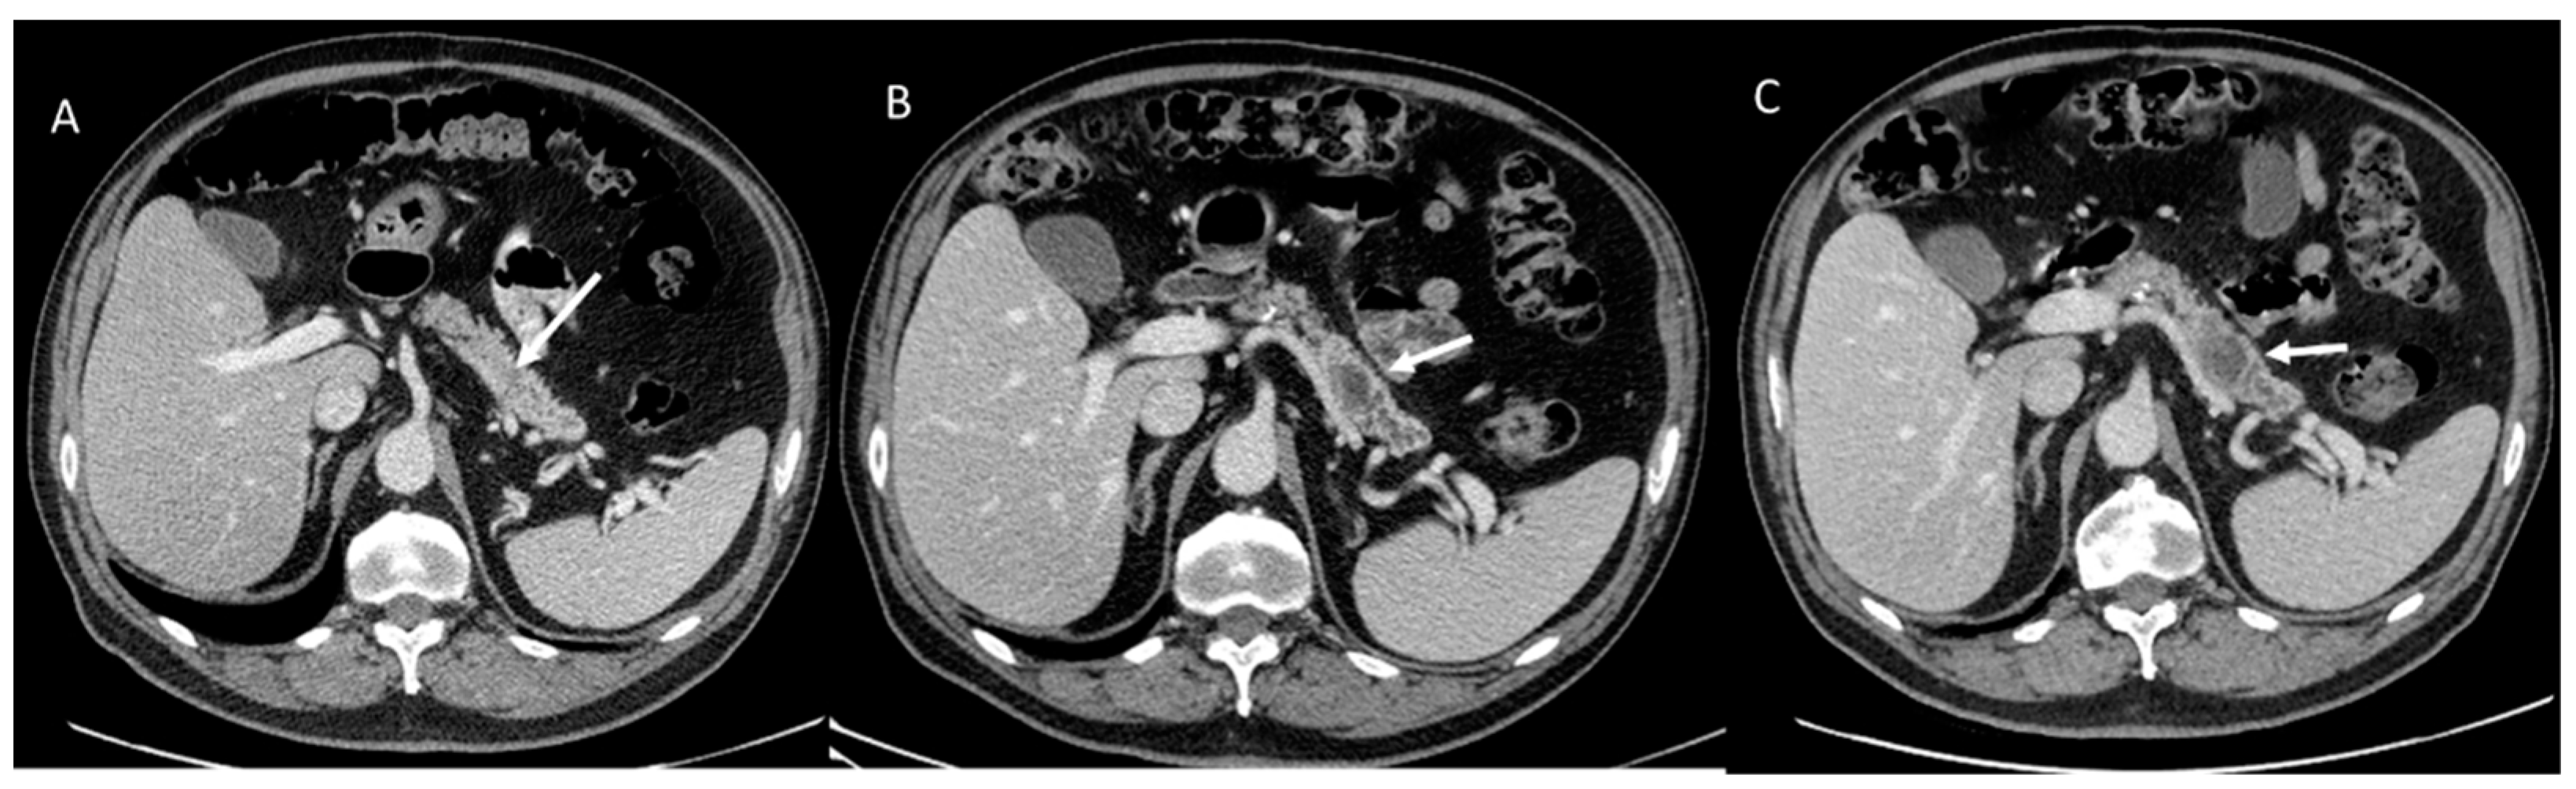

- Granata, V.; Grassi, R.; Fusco, R.; Galdiero, R.; Setola, S.V.; Palaia, R.; Belli, A.; Silvestro, L.; Cozzi, D.; Brunese, L.; et al. Pancreatic cancer detection and characterization: State of the art and radiomics. Eur. Rev. Med. Pharmacol. Sci. 2021, 25, 3684–3699. [Google Scholar] [CrossRef] [PubMed]